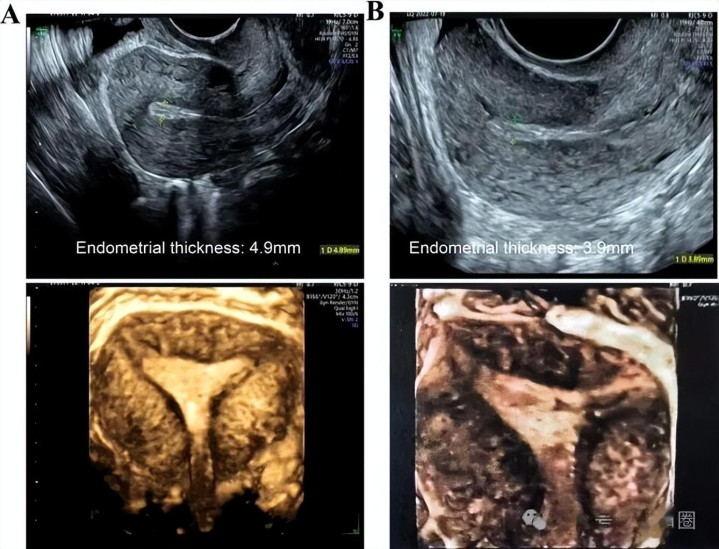

01这位患者的基本情况 患者年事为29岁,就诊于云南省第一东谈主民病院生殖医学科。 2018年至2021年5月间,因多囊卵巢空洞征,她给与来曲唑并吞尿促性腺激素促排卵诊疗,期间经验3次孕8周流产。 最近一次妊娠的胎儿绒毛检测显现拷贝数变异,提醒特纳空洞征。 2019年至2020年间,她在其他病院给与过两次宫腔镜下粘连分辩手术。 宫腔粘连于2019年宫腔镜查抄时被第一次发现,可动力于2018年因流产清宫术形成的子宫内膜损害。 她的AMH为9.66ng/ml,阴谈超声显现子宫大小69mm✖️48mm✖️33mm,双侧卵巢呈多囊样篡改。 患者染色体核型为46xx,对复发性流产有关病因,如免疫身分、血栓前景色、凝血功能、内分泌景色的筛查,未见显赫特殊。 丈夫的精液分析和染色体核型查抄后果亦然宽泛的。 02诊疗的挑战与决策 患者濒临的问题是,到底先促排取卵,照旧先诊疗宫腔粘连? 2021年12月至2022年5月间,患者照旧给与了三次宫腔镜下粘连分辩手术。 手术后,粘连相当容易复发,而恭候有可移植的好胚胎(试管婴儿)也需要时刻。 若是先作念手术松解粘连,在恭候胚胎的几个月里,粘连可能又长上了,手术白作念。 于是医师选择了先取卵,后经管粘连的计策。 这位姐妹试管决策是拮抗剂决策,共获卵21枚,临了形成8个囊胚,经遗传学检测后有4个囊胚可供移植。 这时候医师才入辖下手经管这个患者的粘连问题,这么手术一还原,无意就不错移植胚胎,最大抛弃地裁减了泥土还原好到播撒之间的恭候时刻,阻难粘连复发。 03患者的粘连经管历程 2021年12月至2022年5月间,患者给与了三次宫腔镜下粘连分辩术。 2022年7月,启动口服芬吗通,阴谈使用西地那非,月信第18天内膜仅4.9mm,莫得达标驱逐该周期诊疗,尽管超声显现宫腔时势宽泛,内膜三线征了了。 2022年10月,又不绝下一个周期,月信第三天启动口服戊酸雌二醇和芬吗通,月信收尾后加用西地那非、阿司匹林、宫腔灌输自体富血小板血浆及盆底电刺激。 是以,姐妹们不错看到这位患者基本把临床上所有能用到的主张都用上了,后果若何呢? 月信第14天,阴谈三维超声显现内膜厚度仅3.9mm,华体会体育app另外提醒宫腔粘连可能复发,只可住手诊疗。

2022年11月至2023年3月期间,共行宫腔镜查抄4次,前三次行粘连分辩术,第四次查抄宫腔时势宽泛。 患者作念完粘连手术还放手了三角球囊支架(放手40天),在防患粘连方面阐扬了作用。 另外用透明质酸凝胶隔创举面,也起到了一定的防患再次粘连的作用。 04新的内膜准备决策 当宫腔时势还原宽泛后,就要用药物让内膜长到填塞厚,填塞富饶来招待胚胎。 {jz:field.toptypename/}咱们咫尺常用的决策主要有三种: 当然周期,这适用于本人月信、排卵都宽泛的女性,顺其当然,最接近当然怀胎; 刺激周期,用口服药比如来曲唑、克罗米芬,好像打尿促来和善刺激卵泡滋长,卵泡分泌雌激素让内膜当然滋长; 激素替代周期,十足用外源性雌激素药物,如补佳乐、芬吗通来浇灌内膜,不依赖自身卵泡,这通常用于排卵不好或内膜本人有问题的患者。 这位患者是多囊,排卵不章程,又有严重的薄型内膜,按理说最稳妥径直用激素替代周期,但她过往用过这个决策,内膜根柢涨不起来,游戏平台第一次4.9mm,第二次仅3.9mm。 这讲明她的内膜对单纯外用雌激素响应很差,很可能因为内膜受过伤,雌激素受体功能照旧变得很差了。 这时候,医师换了一个想路,收受刺激周期,但收受了一个稀奇的药物——他莫昔芬。 05为何是他莫昔芬? 他莫昔芬在传统上是诊疗乳腺癌的药物,起到雌激素抵牾的作用。 然而,它在子宫内推崇为聘用性雌激素受体调节剂。 它不仅能促进卵泡发育(产生优质的内源性雌激素),还能在子宫内膜局部上演雌激素的变装,径直刺激内膜细胞增殖,这已毕了表里双修。 传统促排药克罗米芬因其在子宫内膜的抗雌激素反作用,可能导致内膜变薄,彰着不适用。 来曲唑会责问总体雌激素水平,对内膜滋长也有害。比拟之下,他莫昔芬成为了表面上能既促卵泡,又养内膜的更优解。 探讨标明,在月信期短期使用(如5天),并在排卵或移植前停药,其促内膜增生的收益明确,且未加多胎儿古怪或子宫内膜病变的风险,为临床短期阁下提供了安全依据。 他莫昔芬用在子宫上,它却推崇为类雌激素作用,能径直刺激内膜细胞滋长。 它既能产生内源性雌激素,促进卵泡发育,又能径直在子宫里模拟雌激素作用,双重加厚内膜。 因为用药时刻极短,且移植前已代谢收场,是以不会对胎儿产生影响,安全有保险。 医师让这位患者在月信期先服用他莫昔芬5天,启动卵泡滋长和内膜自身的雌激素受体,之后再并吞尿促性腺激素和戊酸雌二醇。 表里结合,双管皆下,最终将内膜从不及5mm增厚到7mm的移植规范。